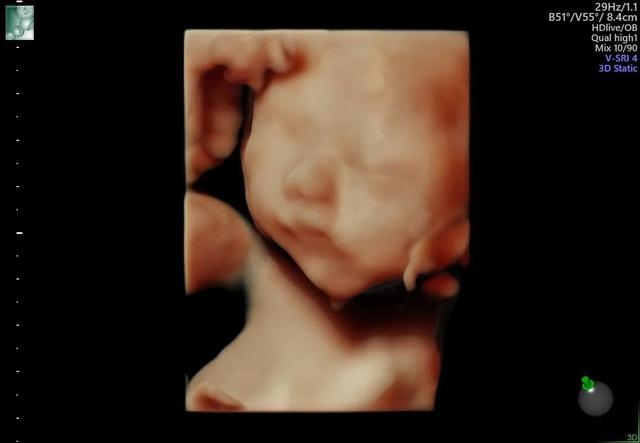

下面是我男宝宝的照片,不爱笑 可能和我脾气不好有原因吧,脾气在调理中。怀孕了还要照顾大宝 照顾家务 实在力不从心。这次怀孕特别累但是也很期待他的出生。预产期是十一月初。